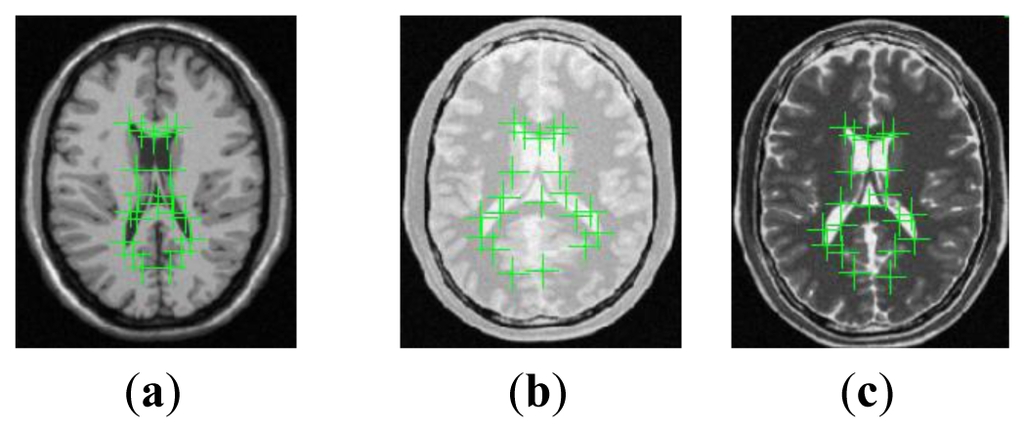

In this section, to determine the key parameters in the proposed method and make comparisons of registration performance among our method, the NMI method, the CMI method, the ESSD method and the ESSD-NMI method, extensive experiments have been performed on thirty T1, T2 and PD-weighted MR images of size 256 × 212 pixels from the BrainWeb database [45]. Registration efficiency of all these evaluated methods is appreciated by their computation time (in seconds) when implemented in a multi-resolution way by rescaling the FFD grid spacing 2k × 2k (each image is rescaled to a square of size 2 to the kth power) [8] using MATLAB 2010 on a personal computer with 2.40 GHz CPU and 4 GB RAM. Registration accuracy is appreciated by target registration error (TRE) [46] with simulated deformation and expert landmark annotations as ground truth, respectively.

As regards the simulated deformation Ts, it is used as the ground truth to deform one of two different weighted MR images (e.g., T1 and T2). By implementing the various registration methods on the float image and the generated reference image, the estimated deformation Tc will be obtained. Based on the whole image domain, TREd is computed as:

When we use expert landmark annotations as ground truth, for a estimated deformation Tc and a set of anatomical landmark pairs (i=1, 2,···, m, where m is the number of anatomical landmarks), TREl is defined as: